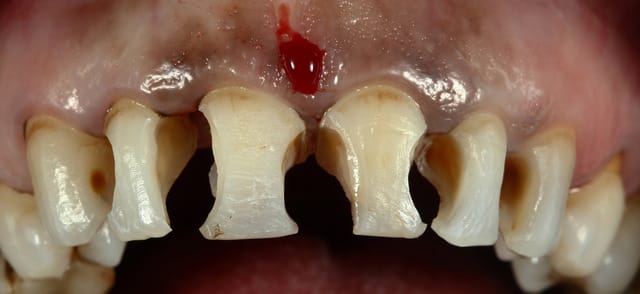

un cas fait hier, Enamel HRI pour la dentine et Esthelite pour l'émail

les zone brunes pox gingivales tu les as polies a quoi ?

bagues rouges, puis disque, puis meulette